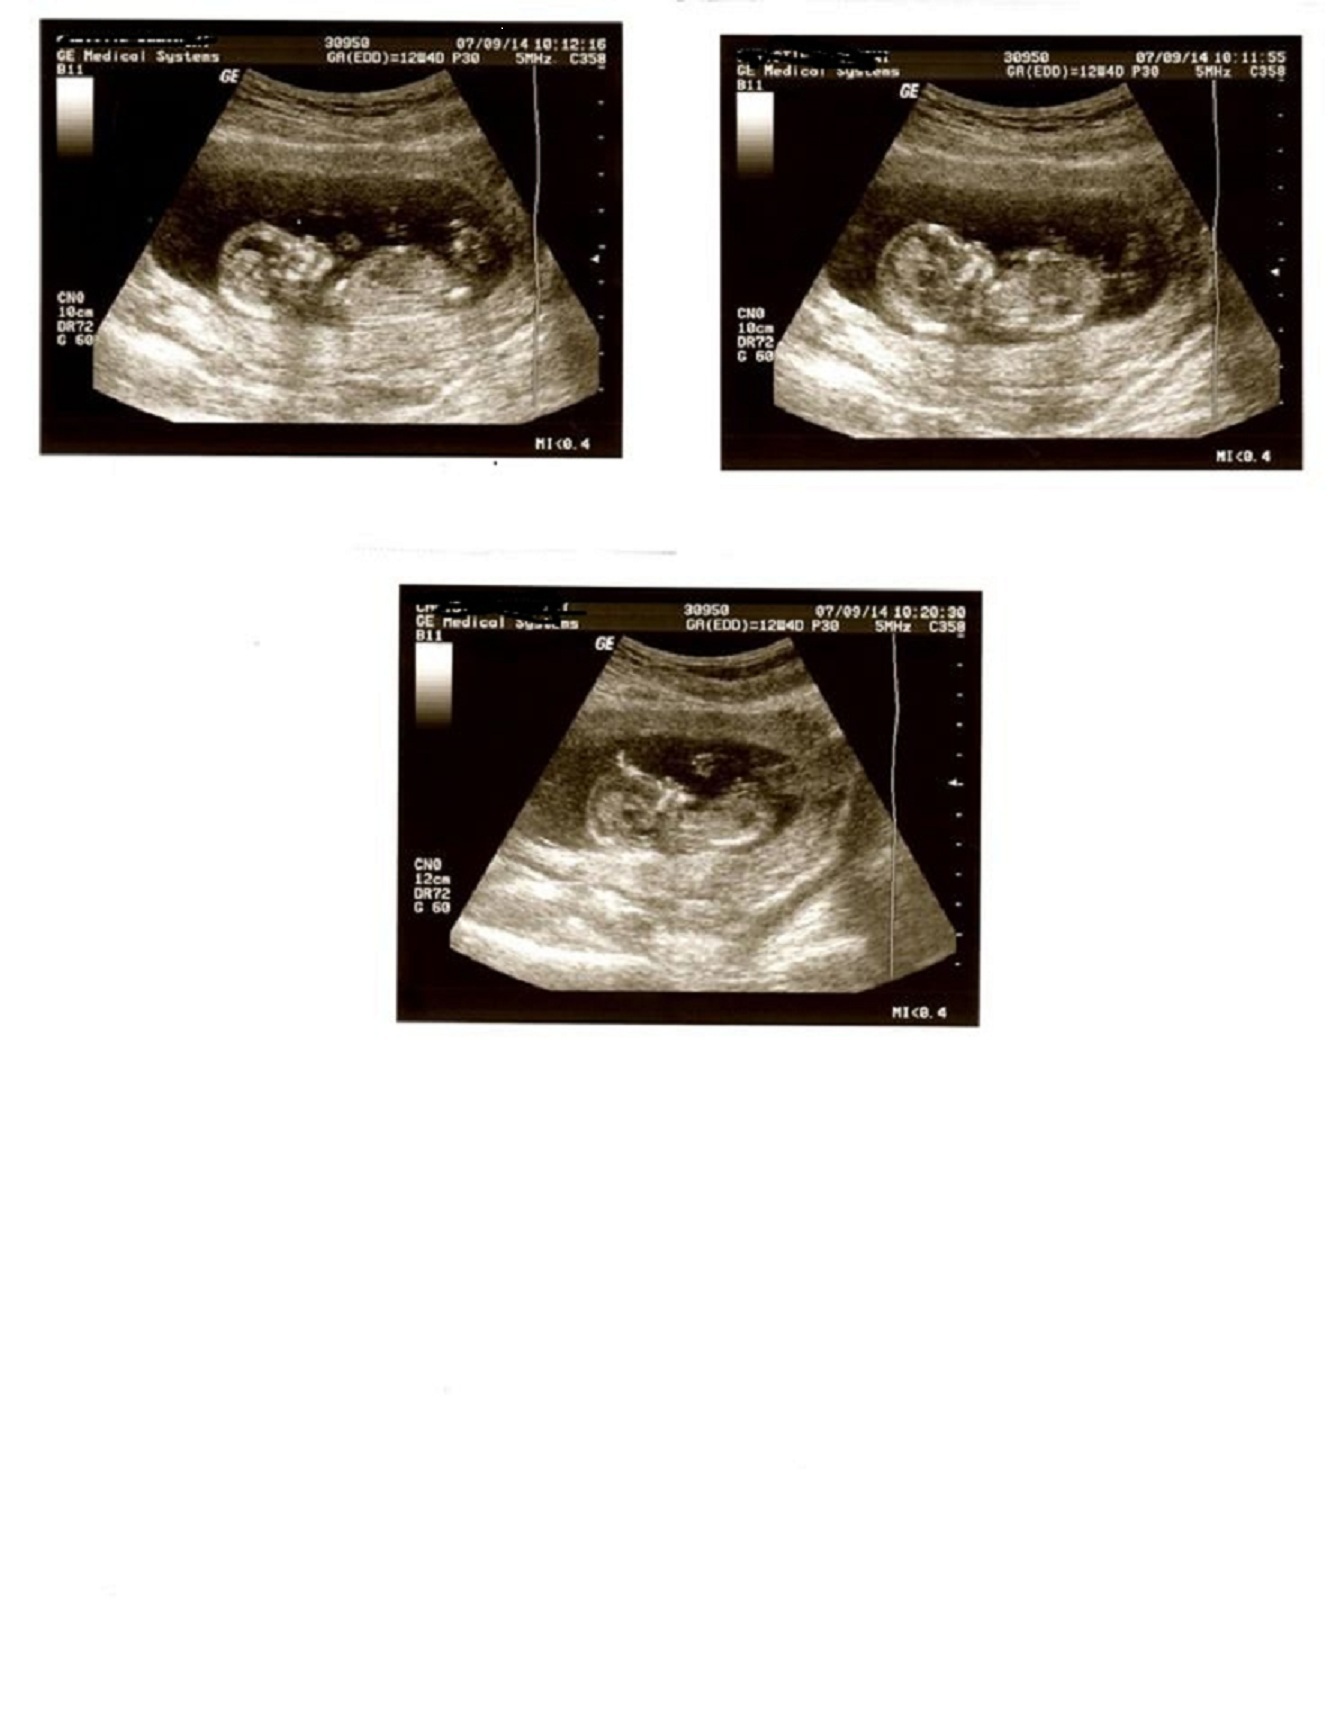

12w4d. Boy or Girl?